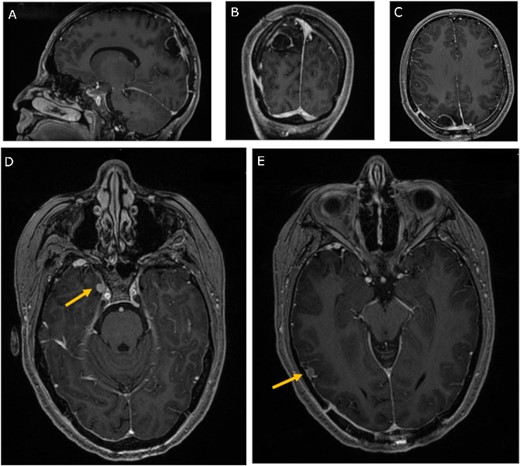

A 19-year-old woman presented with 2 months of intractable holocephalic headaches associated with nausea, occasional emesis, and generalized weakness which worsened over the 5 days preceding presentation. She had no past medical history and was not taking any regular prescribed medications. A computed tomography (CT) head (Fig. 1) revealed a right parietal mass measuring 6.2 × 5.5 × 5.8 cm. Her magnetic resonance imaging (MRI) re-demonstrated a large right parietal extra-axial mass as well as similar lesions in the right temporal lobe, with diffuse increased T1 signal without corresponding enhancement (Fig. 2).

Preoperative MRI; (A) pre-contrast, (B) post-contrast T1-weighted, and (C) T2-weighted axial MRI scans show a large right parietooccipital extra-axial mass with diffusely increased T1 signal without corresponding enhancement; (D, E) axial post-contrast T1-weighted MRI scans show two discrete lobular lesions along the medial aspect of the right temporal lobe and posterior cortical surface of the temporal lobe respectfully.